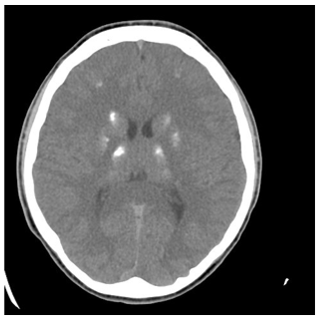

Seizure-Like Activity in an Adolescent with Fahr Syndrome

Sara Farran, Farah Al-Bitar and Berrin Ergun-Longmire. 13(8): 01-05.